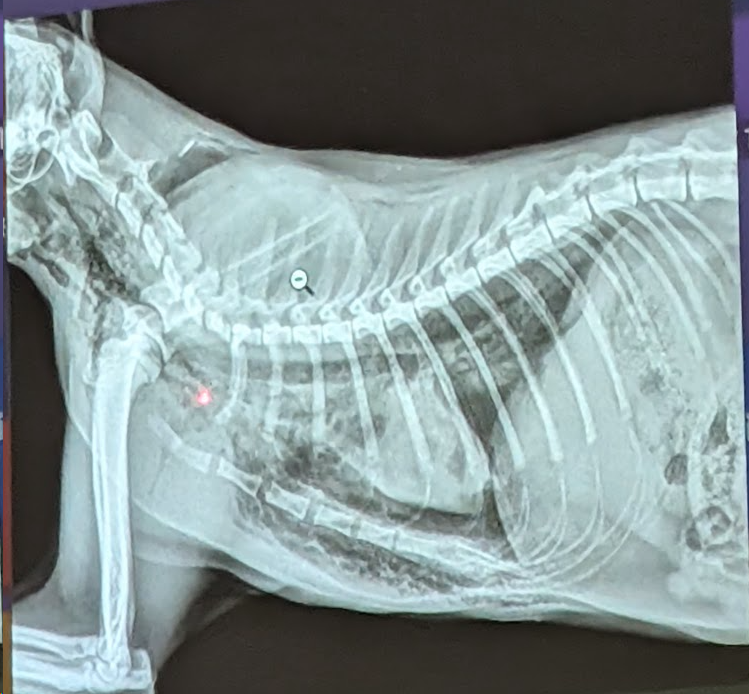

Preguna 2 - Multiple respuesta

- Se trata de un abdomen de perro

- Dilatacion gastrica

- Cuerpo extraño en el estomago (Linea radiopaca en el piloro)

- Eje gastrico alterado.

- Cumple dos criterios de hepatomegalia. (El higado ocupa mas parte, avanzando mas costillas, desplaza al estomago)